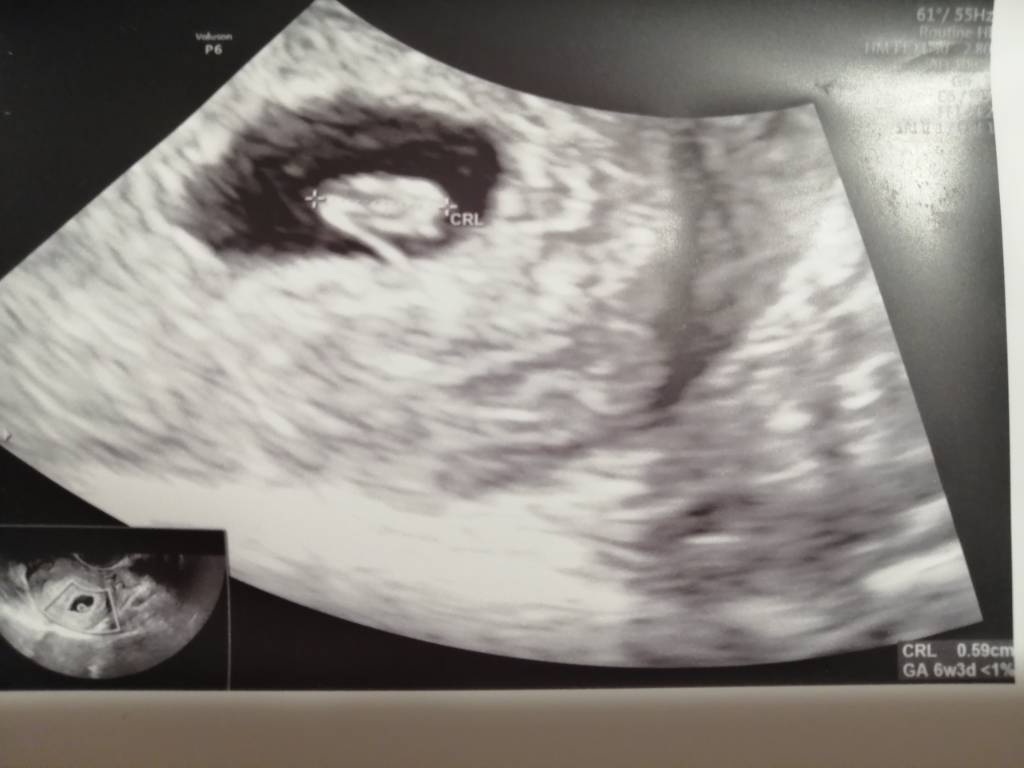

Stawiam na dziewczynkę@Najeczka spójrz na te moje. W ogóle według mnie to dwie inne ciąże [emoji23] a niby ta sama... Widzisz coś? Zobacz załącznik 1016478Zobacz załącznik 1016479

Jestem w ciąży, dzidzius ma 8mm

I pięknie bijące serduszko [emoji813]️[emoji813]️

Termin na 20kwietnia [emoji178][emoji178][emoji110][emoji110]